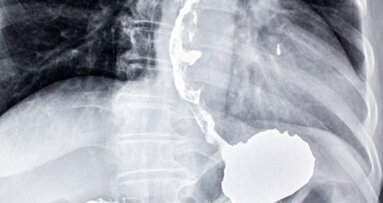

È sempre più attuale e dibattuta dalla comunità scientifica la sostituzione di elementi in zona estetica con impianti ...